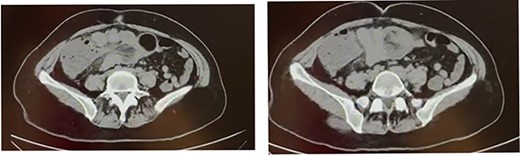

We present the case of a 56-year-old woman with a history of laparoscopic cholecystectomy and arterial hypertension under treatment; the patient had a polyp at the level of the hepatic flexure of the colon diagnosed 5 months before the presentation. She presented to our center with a 4-day history of colicky abdominal pain of low intensity that increased gradually. The pain was mesogastric and radiated to the left hemiabdomen and was accompanied with a sensation of an abdominal mass. On physical examination, vital signs were within the normal range with no abdominal distension. The patient showed tenderness in the mesogastrium and right hypochondrium; a mass was palpable in the mesogastrium with slight pain on palpation and no flatulence. Laboratory analysis showed a leukocyte count of 12 300 × 103/μl. Abdominal tomography showed colo-colonic invaginations involving the hepatic flexure and transverse colon (Fig. 1).

Computed tomography scan shows colo-colonic invagination with the ‘target sign’ or ‘doughnut sing’.

The patient was prepared for laparotomy considering the intussusception involving the ascending colon and hepatic flexure up to the middle of the transverse colon with wall edema and hypoperfusion areas that could not be reduced manually (Fig. 2A and B). The patient underwent right hemicolectomy with ileotransverse anastomosis and was subsequently transferred to the recovery room. The ERAS protocol was applied, with food tolerated after 24 hours, and the patient was discharged on Day 4. The intact sample was sent for pathology.

(A) The presence of an invaginating mass in the colon. (B) Colo-colonic intussusception involving the ascending colon, hepatic flexure and transverse colon.